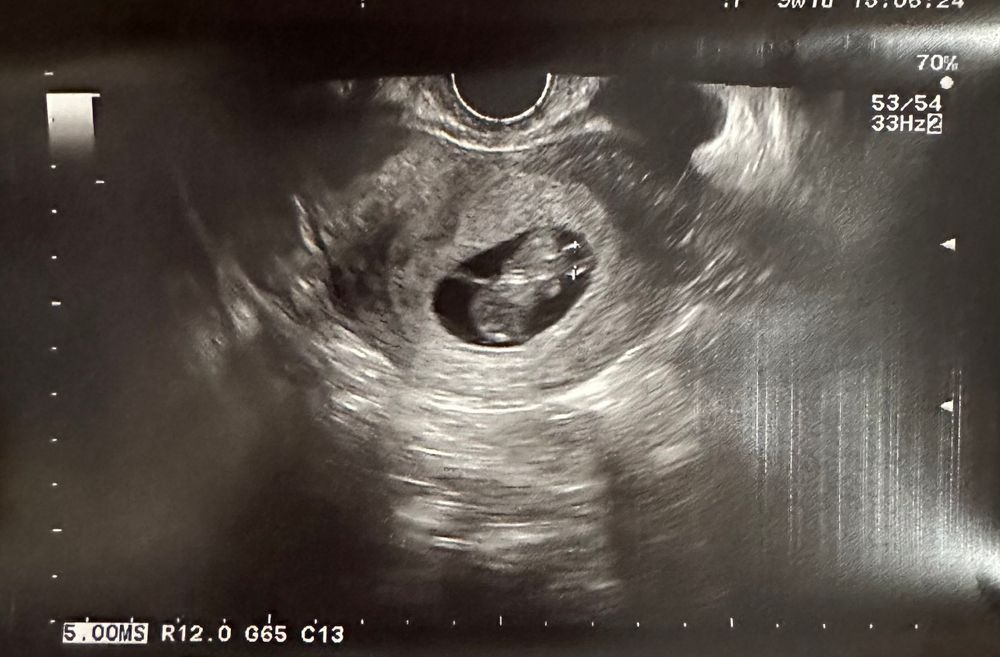

Сходила на Узи…9нед 1день

КТР27 мм, соответствует сроку 9нед 4дня

а вот в этот раз посчитали не диаметр ПЯ, а СВД. На прошлом узи и на этом очетливо видно, что ПЯ не деформировано, но немного уплощено! Нигде не нашла про это информации

ПЯ получается 3.9*2.8*3.6, из-за этого среднее получается каким-то маленьким всего 3.43

если из этого среднего вычесть КТР- свободного места для малыша остаётся 7мм

Вот СВД мерили-он аж на срок 8нед3дня только тянет. А просто диаметр 39мм(прошлое узи 27мм)-то есть за 12 дней выросло ровно на 12мм